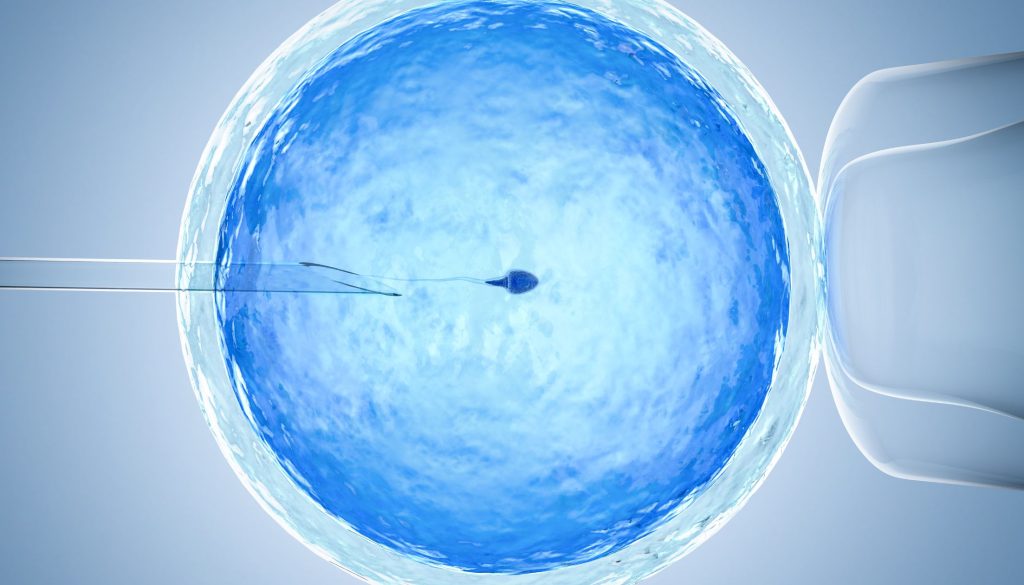

نصائح طبية وتعليمات تثقيفيه بخصوص الحقن المجهري و التلقيح الصناعي

الحقن المجهري والتلقيح الصناعي من أساليب التكنولوجيا الطبية الحديثة التي قدمت حلولاً فعّالة للعديد من الأزواج الذين يواجهون صعوبات في الحمل بشكل طبيعي. بينما يبدو أن كلتا العمليتين معقدة وقد تكون مخيفة للبعض، إلا أن الفهم الجيد للمراحل والإجراءات والنصائح الطبية يمكن أن يساهم بشكل كبير في تحسين تجربة المرضى ورفع فرص النجاح.

الحقن المجهري، المعروف أيضًا باسم Injection Intracytoplasmic Sperm، يتضمن حقن حيوان منوي واحد مباشرة داخل البويضة. من ناحية أخرى، التلقيح الصناعي أو التلقيح في النساء (IVF) يشمل جمع البويضات والحيوانات المنوية ودمجها خارج الجسم في المختبر. في السنوات الأخيرة، قدّر أن نسبة نجاح التلقيح الصناعي والحقن المجهري تصل إلى حوالي 40-45% للنساء تحت سن 35، مع تباين النسبة بالاعتماد على عوامل متعددة مثل العمر والصحة العامة.